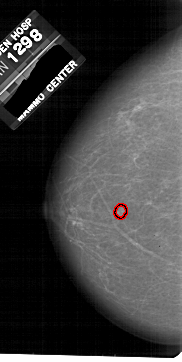

A_1812_1.RIGHT_CC

RIGHT_CC LINES 5491 PIXELS_PER_LINE 2986 BITS_PER_PIXEL 12 RESOLUTION 43.5 NON_OVERLAY